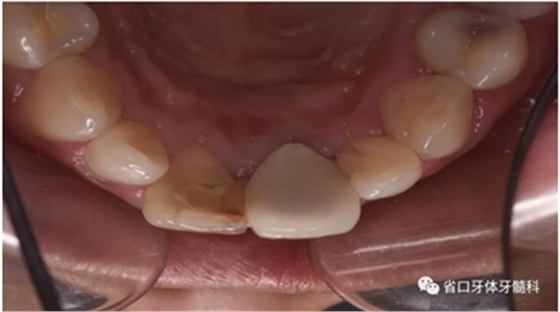

口腔檢查:口腔衛(wèi)生狀況一般,11牙冠變色,近中鄰面見齒色填充物,舌側(cè)窩內(nèi)見白色充填物,邊緣見黑色齲壞物,近中探及懸突,叩痛(土),松(—),冷診無反應(yīng);21烤瓷全冠修復(fù),烤瓷冠顏色未知,唇側(cè)齦緣發(fā)黑,叩痛(土),松(—)。圖1/2

圖1 治療前患牙唇側(cè)觀

圖2 治療前患牙舌側(cè)觀